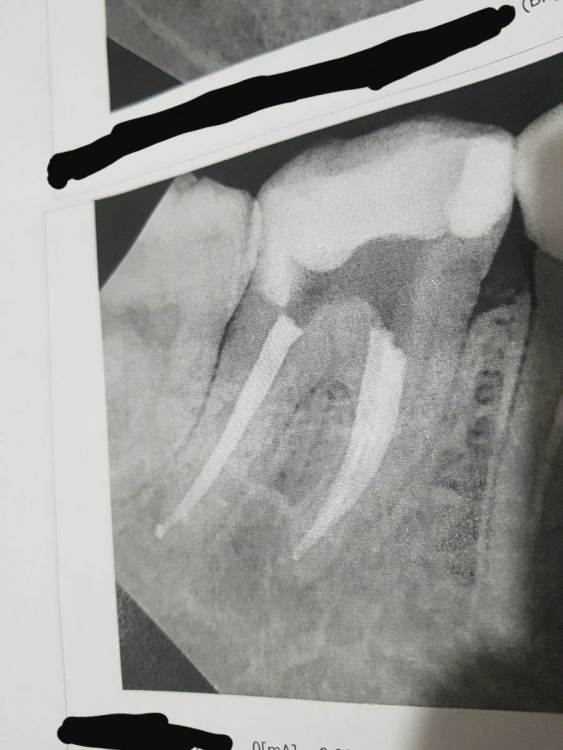

Carioznik Опубликовано 29 мая, 2022 Поделиться Опубликовано 29 мая, 2022 28.05.2022 в 04:42, Александра117 сказал: материал вышел за пределы корня У Вас грамотный доктор, некоторые бы сказали: "идеально! все чётко до верхушки, ничего не вышло". Но то, что вышло в одном из 3 каналов - это такие микроскопические количества, которые ни на что не влияют. Вот, взгляните, когда действительно много вышло (но даже при таких количествах, прогноз, в большинстве случаев, будет благоприятный): 2 Ссылка на комментарий

Александра117 Опубликовано 1 июня, 2022 Автор Поделиться Опубликовано 1 июня, 2022 29.05.2022 в 08:11, Carioznik сказал: У Вас грамотный доктор, некоторые бы сказали: "идеально! все чётко до верхушки, ничего не вышло". Но то, что вышло в одном из 3 каналов - это такие микроскопические количества, которые ни на что не влияют. Вот, взгляните, когда действительно много вышло (но даже при таких количествах, прогноз, в большинстве случаев, будет благоприятный): А в таком случае, как на фото, то, что вышло за пределы, рассосется или так и останется? Ссылка на комментарий

Бардо Опубликовано 1 июня, 2022 Поделиться Опубликовано 1 июня, 2022 24 минуты назад, Александра117 сказал: А в таком случае, как на фото, то, что вышло за пределы, рассосется или так и останется? Зависит от материала. Но даже такая ситуация обычно не повод для паники - наблюдаем и всё. Как правило, пациента ничего не беспокоит, сами по себе современные материалы достаточно инертные 1 Ссылка на комментарий

Гарриевич Опубликовано 4 июня, 2022 Поделиться Опубликовано 4 июня, 2022 01.06.2022 в 16:06, Александра117 сказал: А в таком случае, как на фото, то, что вышло за пределы, рассосется или так и останется? Зависит от типа выведенного материала (силера). Рассасывается это от 15 до 100%, но в 100% не несёт в себе никакой опасности Ссылка на комментарий